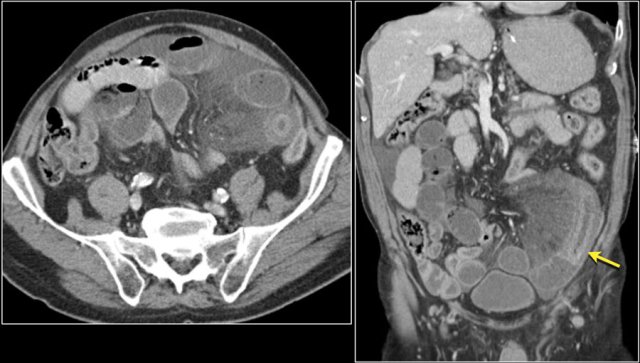

Here a patient with metastatic melanoma.

Left image shows ileal-ileal intussusception due to metastasis.

Right image shows intussusception in coronal plane as well as an enlarged mesenteric lymph node (yellow arrow) and extensive liver metastases.